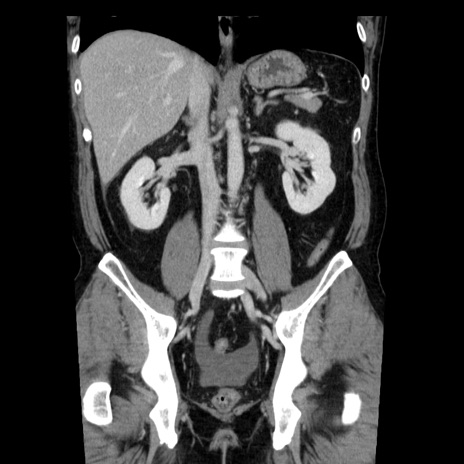

症例29(冠状断像)

【症例】40歳代男性

【現病歴】2日前から胃痛あり。徐々に周期的な激痛に変化した。本日になっても激痛があるため受診。

【身体所見】意識清明、BT 38-39℃台あり、腹部:膨満、やや硬、右下腹部に圧痛あり。

【データ】WBC 8500、CRP 23.26